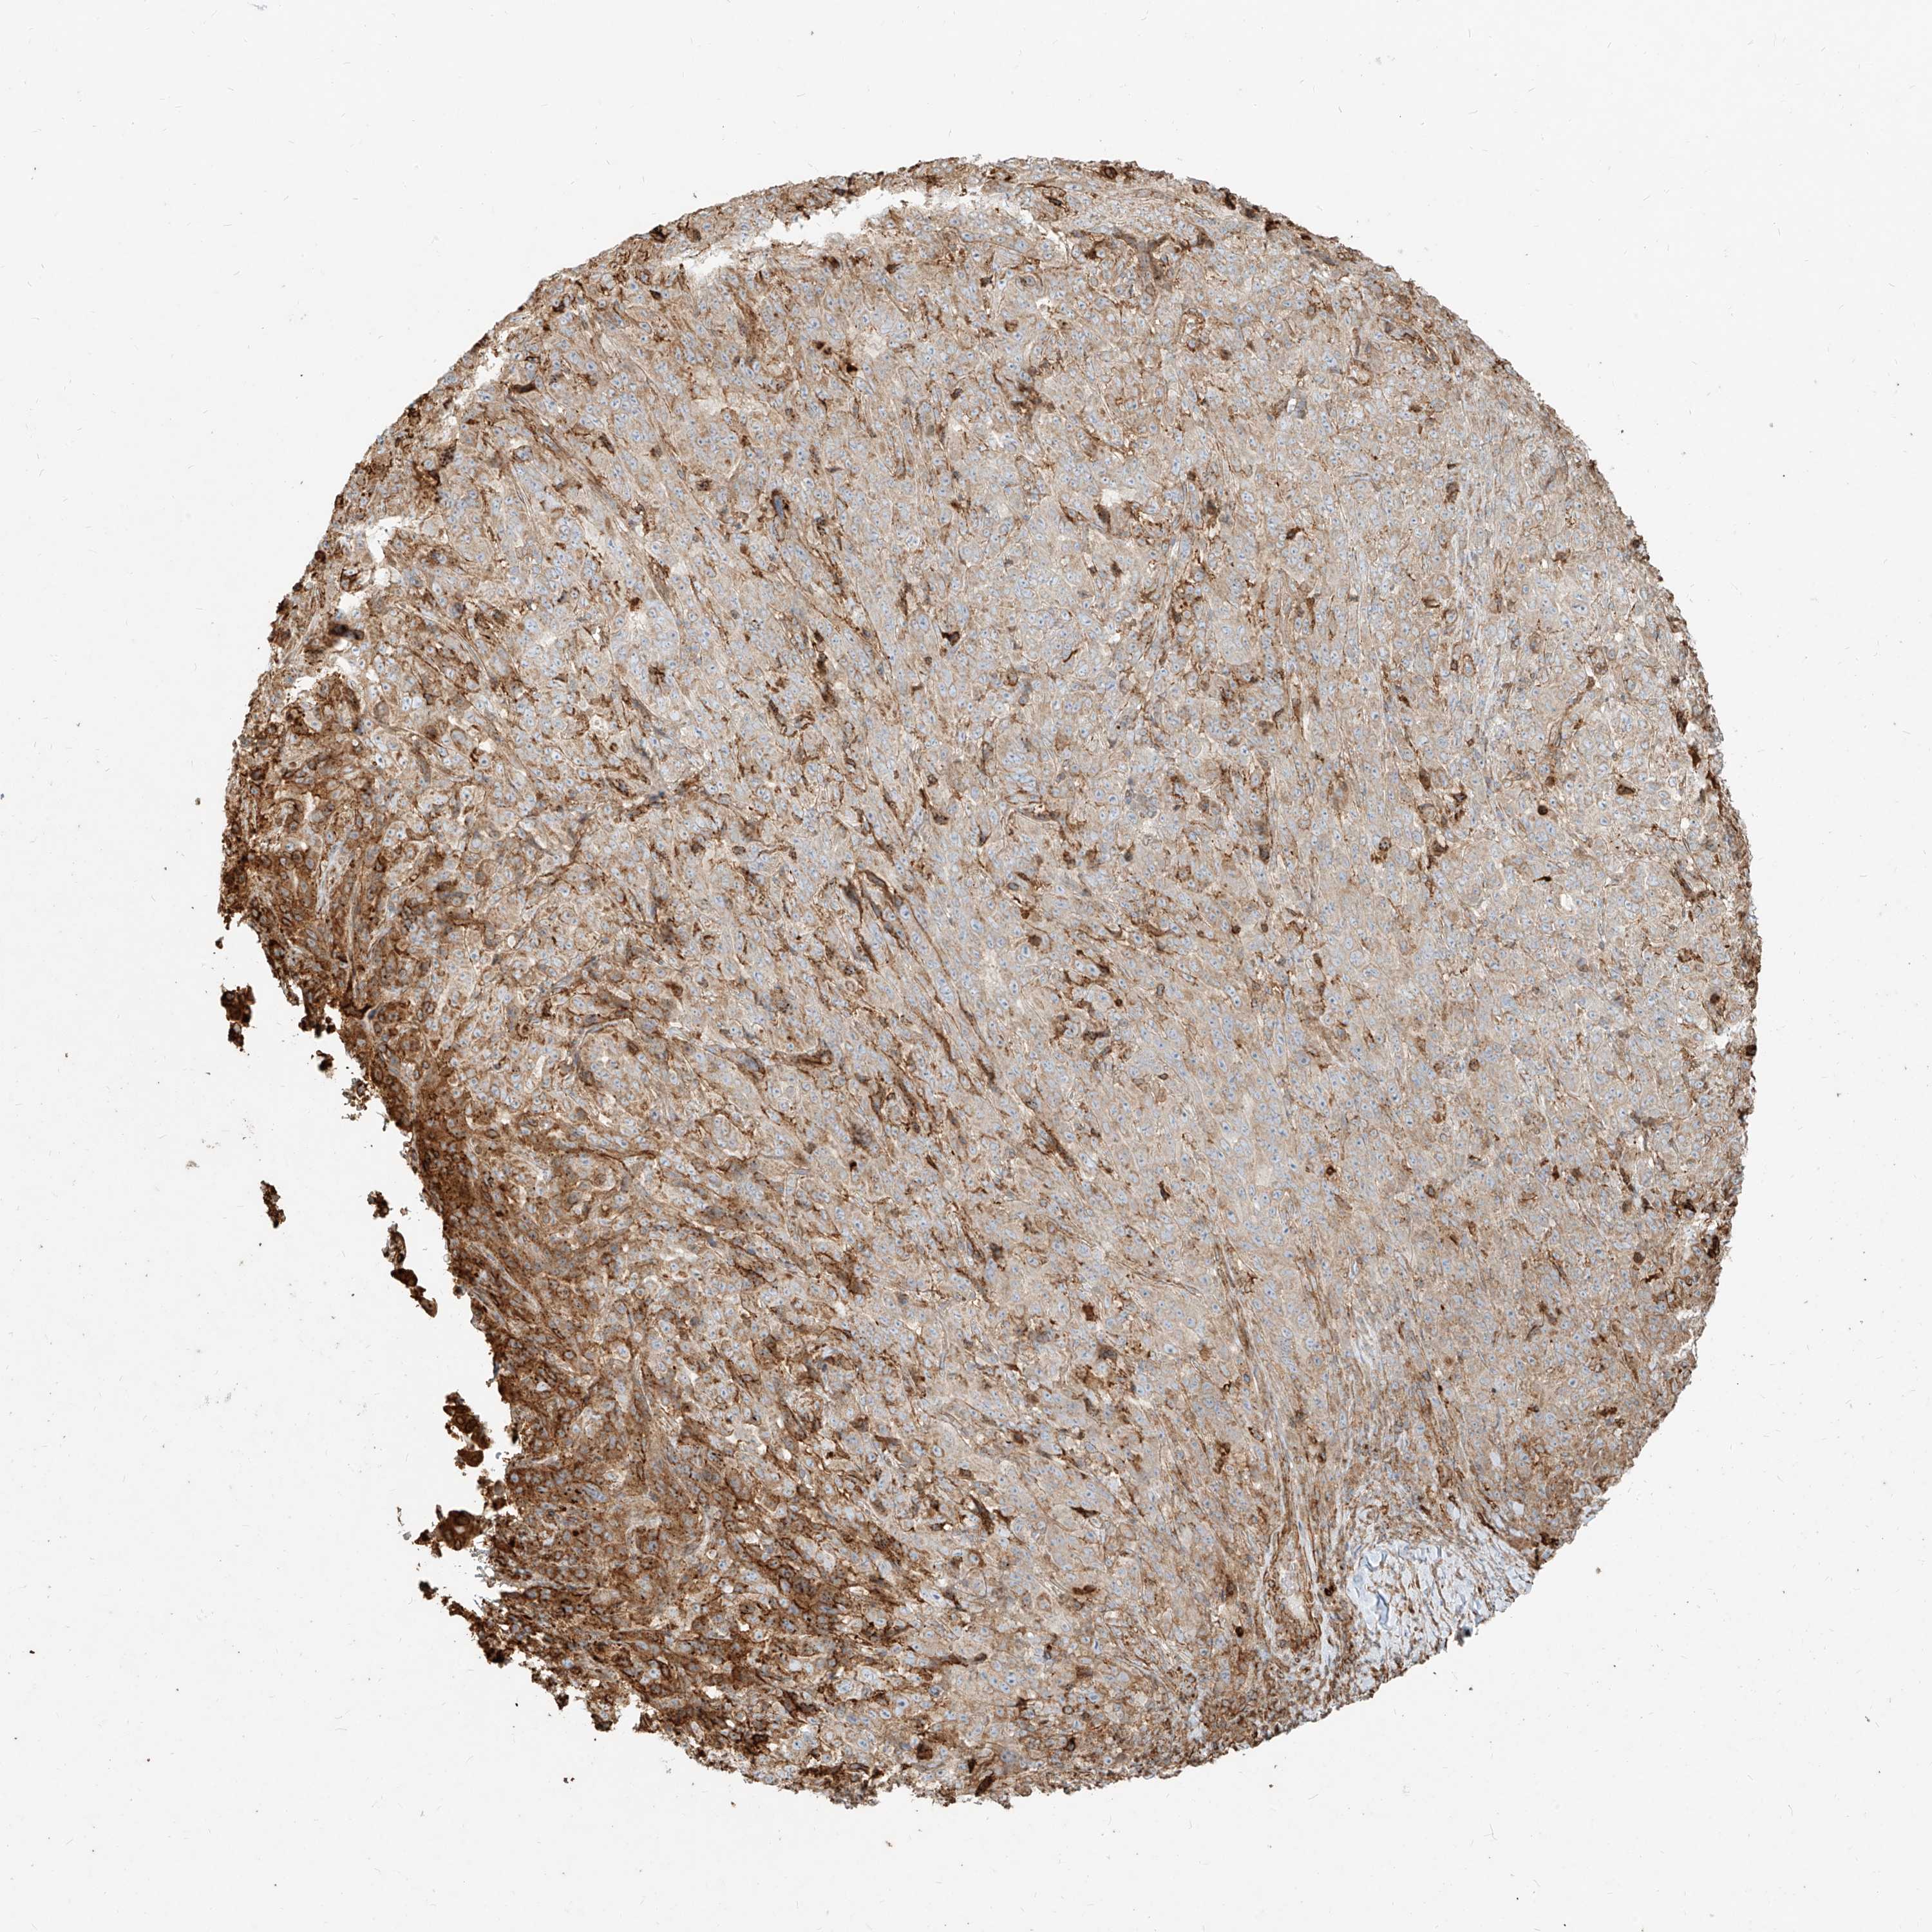

PANCREATIC CANCER - Protein expressioni

A mouse-over function shows sample information and annotation data. Click on an image to view it in a full screen mode. Samples can be filtered based on level of antibody staining by selecting one or several of the following categories: high, medium, low and not detected. The assay and annotation is described here.

Note that samples used for immunohistochemistry by the Human Protein Atlas do not correspond to samples in the TCGA dataset.

Antibody stainingi

Antibody staining in the annotated cell types in the current human tissue is reported as not detected, low, medium, or high, based on conventional immunohistochemistry profiling in selected tissues. This score is based on the combination of the staining intensity and fraction of stained cells.

Each image is clickable and will lead to virtual microscopy that enables deeper exploration of all samples and also displays staining intensity scores, fraction scores and subcellular localization as well as patient and tissue information for each sample.

Antibody HPA031550

Antibody HPA031551

Antibody HPA031552

Staining

High

Medium

Low

Not detected

Intensity

Strong

Moderate

Weak

Negative

Quantity

>75%

75%-25%

<25%

None

Location

Nuclear

Cytoplasmic/membranous

Cytoplasmic/membranous,nuclear

Adenocarcinoma, NOS